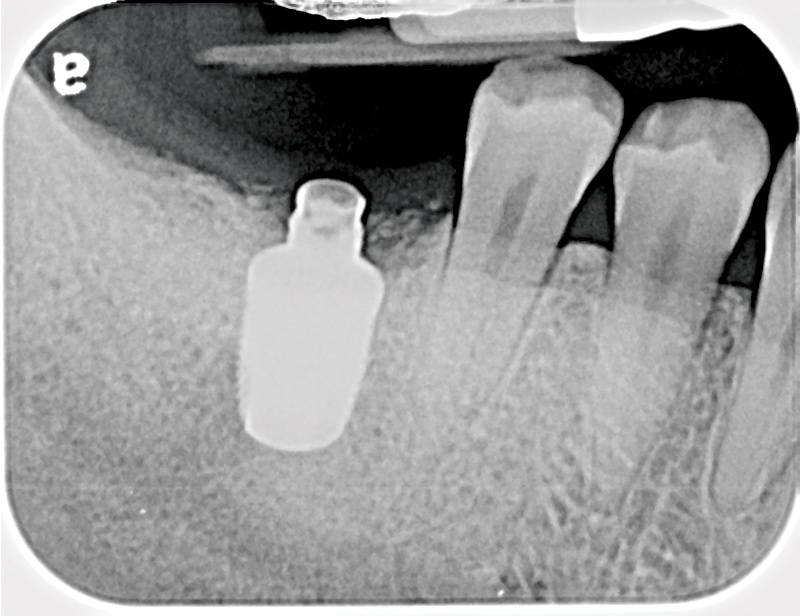

Fig 16. Radiograph depicting closed contact at time of implant insertion.

Figure 16

Fig 17. Open proximal contact between implant and adjacent tooth 3 years post insertion.

Figure 17